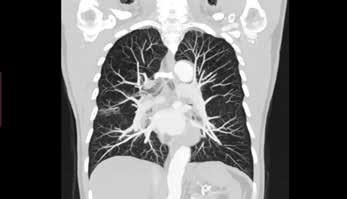

Photon-counting computed tomography (PCCT) promises to revolutionise CT imaging by substantially increasing spatial resolution and iodine contrast conspicuity, reducing radiation dose and beam hardening artifacts, and allowing spectral imaging with multiple energy bins.

Unlike traditional energy integrating detectors which use solid-state scintillators to first convert X-ray photons to light, photon-counting detectors use a semiconductor material to directly convert incoming X-rays to an electric signal in a single step. Each photon gives rise to a voltage that is proportional to its energy, allowing energy discrimination on the basis of voltage comparison. A count can therefore be assigned to the bin that matches the photon’s energy range, hence the name “photon counting”. With enough bins, one can therefore perform spectral analysis of the incoming photon flux, and extract spectral information for quantitation or material decomposition. Since lower energy photons, which produce more contrast information, get equal weighting to higher energy ones, the images have improved contrast resolution.

Prof Roland Bammer, Head of Monash University’s Department of Imaging*, describes this transition. “Remember the times when you were watching sports on a low-res black and white TV with the “bunny ears” on top? Now you can watch events in colour on your 4K TV. This is the paradigm shift in CT that’s currently happening with photoncounting. The ‘colour’ depth isn’t OLED quality yet, and more like on the old CGA or VGA monitors, but it’s there. You can do all the interesting things energy integrators can’t do without dual kV source or kV switching. PCCT does the energy discrimination on the

detector side, and opens up a new field in radiology.”

Although it has long been known that photon counting is the most efficient approach to X-ray detection for CT, developing a direct conversion material which can handle the high X-ray photon flux of CT has been the major challenge. Prof Bammer says “Whether the future of photon-counting CT will lie in cadmium telluride (CdTe), cadmium zinc telluride (CZT), or silicon (Si) semiconductors is still unclear. The jury is still out. The individual vendors seem to have made bets on different semis. Each material has its strengths and weaknesses, and the vendors have learned to leverage the strengths of their material and minimise the impact of its weaknesses. The upcoming RSNA will therefore be very interesting. We might see more vendors entering this space. I believe independent research— outside the corporate labs—is warranted to get to the bottom of it. Once more systems are installed, it will help us to provide the evidence base on real-world performance in clinical settings. Whether it’s the more difficult to manufacture but highly efficient CdTe semis, or the more broadly available, cheaper silicon substrate, is superior, of one thing I am confident: we will see a lot of innovation and new clinical applications in that space in the near future. It’s another big fork in the road for CT, similar to when spiral or multi-detector row CT were introduced. I am therefore very excited about this technology.”

Physicist Dr Christian Schroeter, PhD, who led the effort to develop the direct conversion detector material for Siemens Healthineers, talks to Associate Professor Shalini Amukotuwa, PhD, MB BS, FRANZCR (Head of Diagnostic Neuroradiology and MSK at Monash Health) about the detector and his experience in developing it.

Photon-counting detectors have brought about a paradigm shift in CT imaging. Can you tell us what the main advantages of this technology are, compared to the conventional CT scanners which we are currently using?

There are several technical advantages: higher spatial resolution, elimination of electronic noise, radiation dose efficiency and, last but not least, spectral information, not only in every image, but also everywhere in the image. Improvement in these crucial technical parameters translates to clinical benefits, which we have been working on since the prototype phase. We have already seen that there are certain things that you can only do with a photoncounting CT. For example, a really hot topic is imaging stented coronary arteries. The metallic stents cause a lot of artifacts, due to beam hardening and photon starvation, which obscure the vessel lumen. These patients are therefore often sent to cathlab instead

of CT coronary angiography. Now, with photon-counting CT, we can get really good images of the vessel lumen, to see in-stent details. This is because of the far superior spatial resolution, reduced blooming and beam hardening, and lack of electronic noise, which we can filter out. The spectral information also allows us to obtain material (iodine) images of the vessel lumen, and we can use material decomposition to subtract out any calcified plaques. We are currently exploring whether these images are now accurate enough for catheter angio to be avoided, which will be a big game changer for patients. Another important example is imaging obese patients, and low-dose imaging, where photon counting provides better image quality with less noise because electronic noise is eliminated. The journey has only just begun, and we will continue to see what these technical advantages really mean in clinical practice, since that’s what’s important.

Why did it take so long to develop photon-counting CT scanners? What was the main barrier to overcome?

The direct conversion material for the detector was the main barrier, and we had a long development phase. The project started 20 years ago. We seriously engaged in screening the market of available detector materials around 15 years ago. The first phase was to look at what was already available, then select the best vendor. We identified a company in Japan

The main challenge at that time, 15 years ago, was that most manufacturers used the detector material for gamma cameras, for SPECT, or just spectrometers. The company that we selected already used CdTe detector material for X-ray imaging, although this has a much lower X-ray photon flux than CT. Of all imaging applications, CT has by far the highest X-ray photon flux applied to the detector. The materials which were available then just couldn’t cope with this high flux. There were even scientific papers claiming, based on models, that it may not be possible for CdTe detectors to convert X-rays to photons directly at the typical flux-rates of CT. In the initial prototypes, we could slow down the flux to address this. However, for a clinical full body scanner, you need to be able to work at high flux rates, to be able to deal with any clinical scenario. We were lucky that we came to a point, around 2011, where we could overcome this apparent fundamental hurdle and major impediment which otherwise would have put an end to the project. Another group did actually give

Yes. The solution was based in the CdTe crystal growth itself. You have to go very deep into the very start of the process chain, to the crystal itself, to address the problem of polarisation. You need to understand the whole chain, from crystal growth to image generation, and we saw that many aspects of the crystal growth, for example doping (where tiny amounts of impurities are introduced to alter the crystal structure), the temperature treatment, and the electrodes that we applied, needed to match the bulk material. We had to bring all these pieces together, and understand the signal that comes out of the detector material to design the electronics, the application specific integrated circuit, accordingly. But the trick was really in the first steps, and it was quite a basic one.

Volume 18 No 4 | September 2022 19

So those steps reduced the amount of charge (hole) trapping in the detector material, which is the cause of depolarisation?

Yes. The assumptions, which were made in the models which showed that building a CT detector from CdTe would not be possible, were not as simple as initially thought. The models that we now have, based on our empiric observations and better understanding of the detector material, are quite different. It turns out that hole trapping is not such an issue after all! In fact, it never was a fundamental issue for CdTe, but back then, we didn’t have the knowledge and understanding to have this insight and confidence. Now, the fact that there is a clinical whole-body photon-counting CT shows that the argument that CdTe can’t be used as a detector just doesn’t hold true. We have also seen that there is another company in Canada which is stepping into prototyping at a clinical level using a detector with similar material, CZT. I’m therefore confident that they have also overcome this basic hurdle.

Can silicon detectors work for photon-counting CT?

Spatial resolution is the major weakness of silicon-based detectors, and also radiation dose efficiency because of lower absorption which is due to the lower atomic number. With any detector material, you can, with the right system design, bring out one specific parameter and excel at it. For example, extremely high spatial resolution, energy resolution, or dose efficiency. That is nice for a scientific paper or a prototype, but not for a clinical product. You need to have a holistic approach, and bring together and harmonise these parameters for a clinical scanner. You also need scan speed, which is underestimated, and not just for cardiac applications. Dose efficiency and spatial resolution maybe the most important, but then speed, and then energy information. We worked on this integration and harmonisation for 10 years, starting with prototypes scanners and ending with the final product. In my understanding and firm opinion, silicon just can’t do this.

Do you need more than four energy bins?

We will see. It felt like the end of the journey when we launched the clinical scanner, now it seems like it’s just the beginning. We will see what the clinicians and researchers will find out. But right now, in my opinion, even if you have one threshold, you already have most of the advantages of photon counting, like dose efficiency, high spatial resolution, and absence of electronic noise. If you have two energy bins, you can do iodine separation. With a third bin, then you can do crazy stuff, with new contrast agents such as gadolinium and gold particles, which have a k-edge. It is possible then to make an additional energy separation, but this is a very early, pre-development research topic. The scanner has a fourth bin, so you are future proof in case somebody invents something where you need it. More bins than that are superfluous.